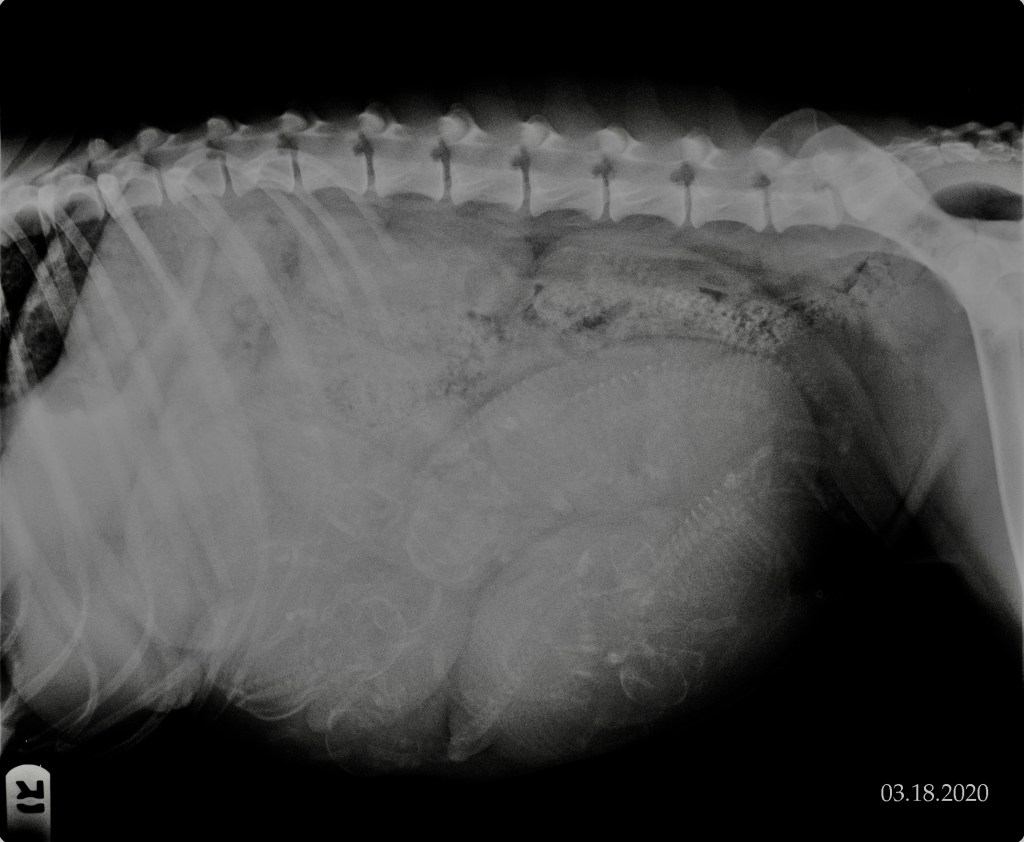

3-18-20

Today we had our repro vet take an x-ray and count how many little puppies she sees inside of Miss Kimb. Before she even took her back to take the picture, she said that she might have the pups sooner than her due date, which isn’t abnormal for a litter this size. She was pleasantly surprised when she saw how well she has been doing. When Dr. Harr came back into the room, she said that she saw 11 puppies for sure, and that maybe a 12th was hiding in there too!

Feel free to comment how many you see; don’t forget to check under her ribs too!